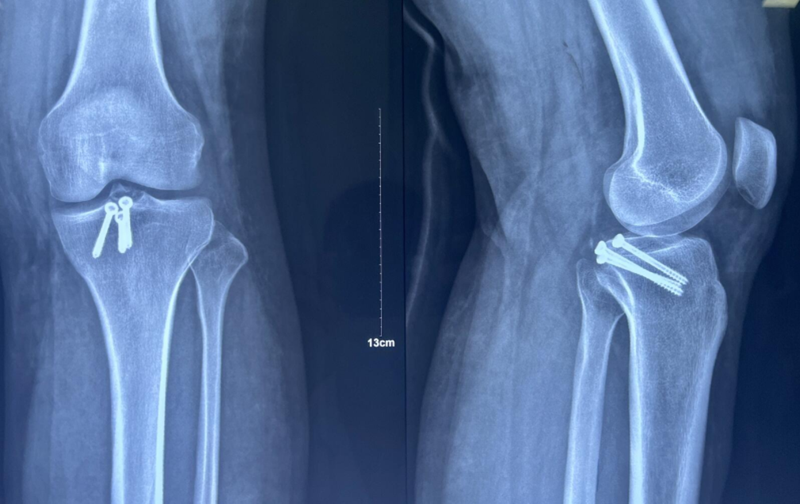

x男,30岁,体重100kg,在五楼擦玻璃时坠落到四楼致伤2天。

诊断:左胫骨平台后柱骨折,后交叉韧带撕脱骨折,左踝关节pilon骨折3型。

术前影像学资料:

图7 前交叉韧带撕脱骨折与平台后柱骨折

图8 Pilon骨折3型